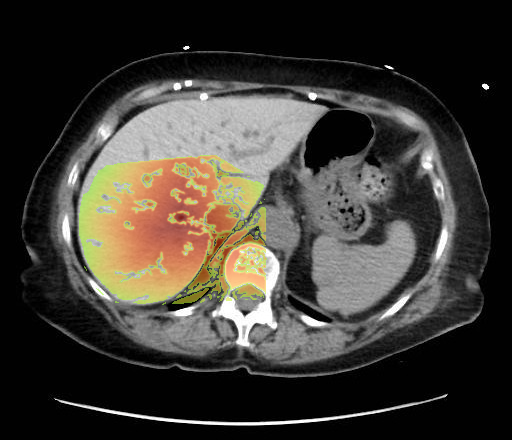

Liver hyperattenuation from Amiodarone

- Non-contrast axial CT through the upper abdomen.

- The liver (image-left, patient-right) demonstrates diffusely increased parenchymal attenuation relative to spleen (image-right, patient-left).

- Liver contour appears smooth, no focal mass identified at this level.

- Spleen (image-right, patient-left) of normal size and attenuation.

- Stomach fundus (image-right, patient-left) partially distended with air-fluid level.

- No ascites visible.

- No intrahepatic or extrahepatic biliary ductal dilatation.

- Osseous structures and visualized lung bases appear unremarkable at this slice.

Diffuse hepatic parenchymal hyperattenuation due to amiodarone deposition (amiodarone liver). The liver is abnormally hyperdense on a non-contrast CT compared to the spleen, which is a classic imaging feature of amiodarone-induced hepatic iodine deposition. The attenuation difference eliminates common diffuse hypodensity causes such as steatosis, iron overload, or Wilson’s disease. Context consistency: Consistent. The uploader’s diagnosis of "Amiodarone Liver" directly matches the imaging appearance. Confidence: 90%.